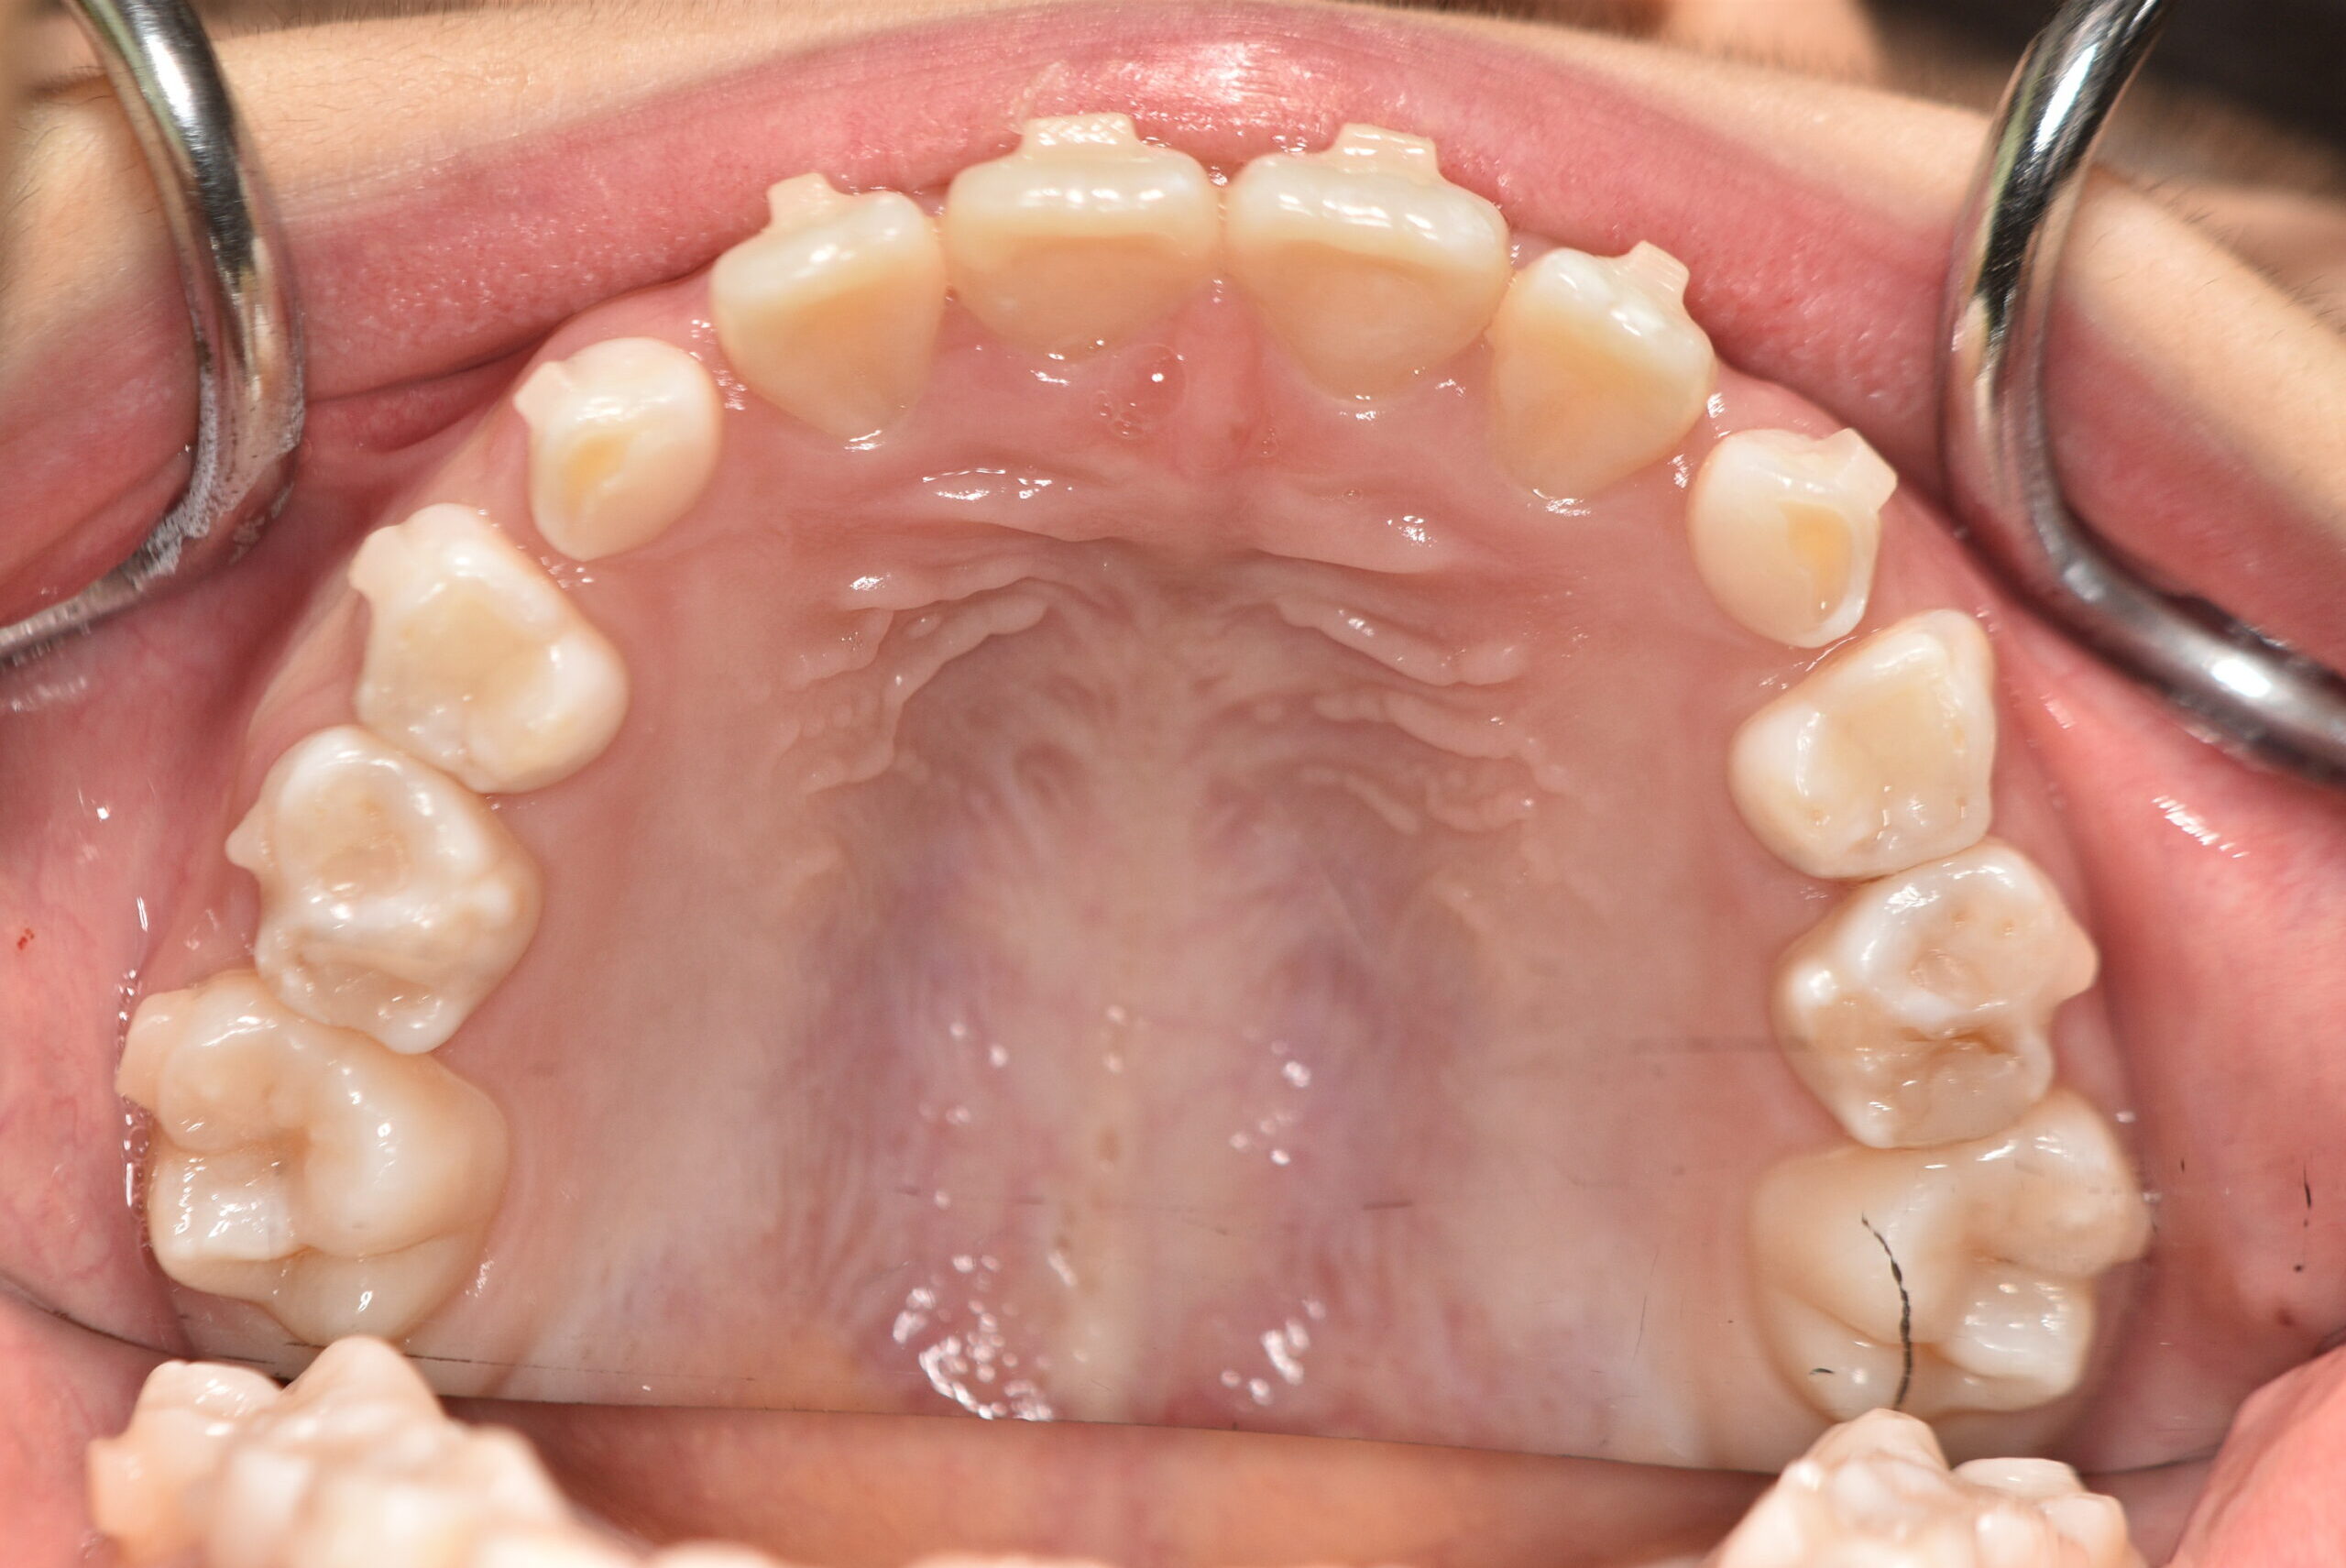

動的治療終了時

症例 症例 症例 症例

治療としてはマウスピース矯正(インビザラインファースト)で配列を行い、上下顎の側方拡大と萌出スペースを確保しました。

治療期間は、7ヶ月でした。

今後、側方歯生え変わりまで経過観察を行います。